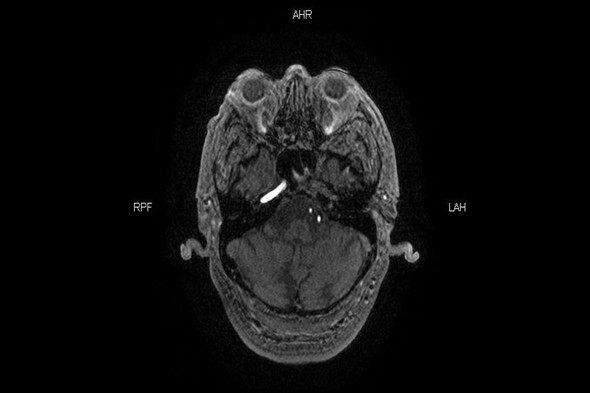

介入科刘琳团队接到通知立即启动脑卒中快速通道,患者准备MR检查的同时介入导管室护士、急诊麻醉师刘洋、赵亮已到位。核磁科崔红升主任团队经过详细的检查分析评估,得出结果为左颈内动脉起始栓塞,颅内小梗塞病灶显影,还有大量可挽救的脑细胞,适合介入取栓治疗挽救患者生命。

MR 左颈内动脉未显影

MR 血管重建左颈内动脉消失,右颈内动脉显影正常